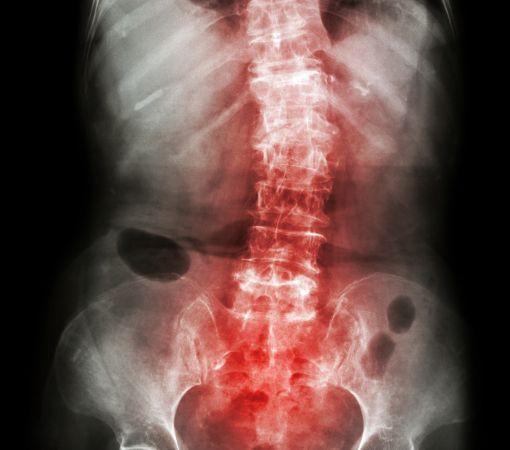

Understanding spondylitis causes helps in finding the right treatment.

Spondylitis, an inflammatory condition that affects the spine and nearby joints, is typically managed through a combination of medication, physical therapy, and minimally invasive procedures. Dr. Ganesh Nagarajan and the team at Synapse Spine employ advanced imaging and diagnostic methods to accurately assess each case, ensuring that patients receive the right combination of therapies. Effective spondylitis treatment in Mumbai at Synapse Spine can include anti-inflammatory medication, guided exercise programs, lifestyle modifications, and, in severe cases, surgical intervention.